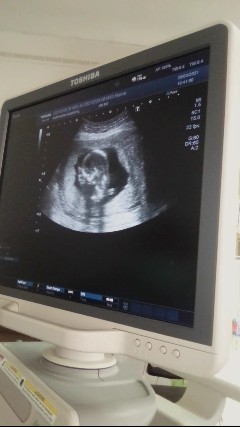

ของเราภาพตอน 12wค่ะ